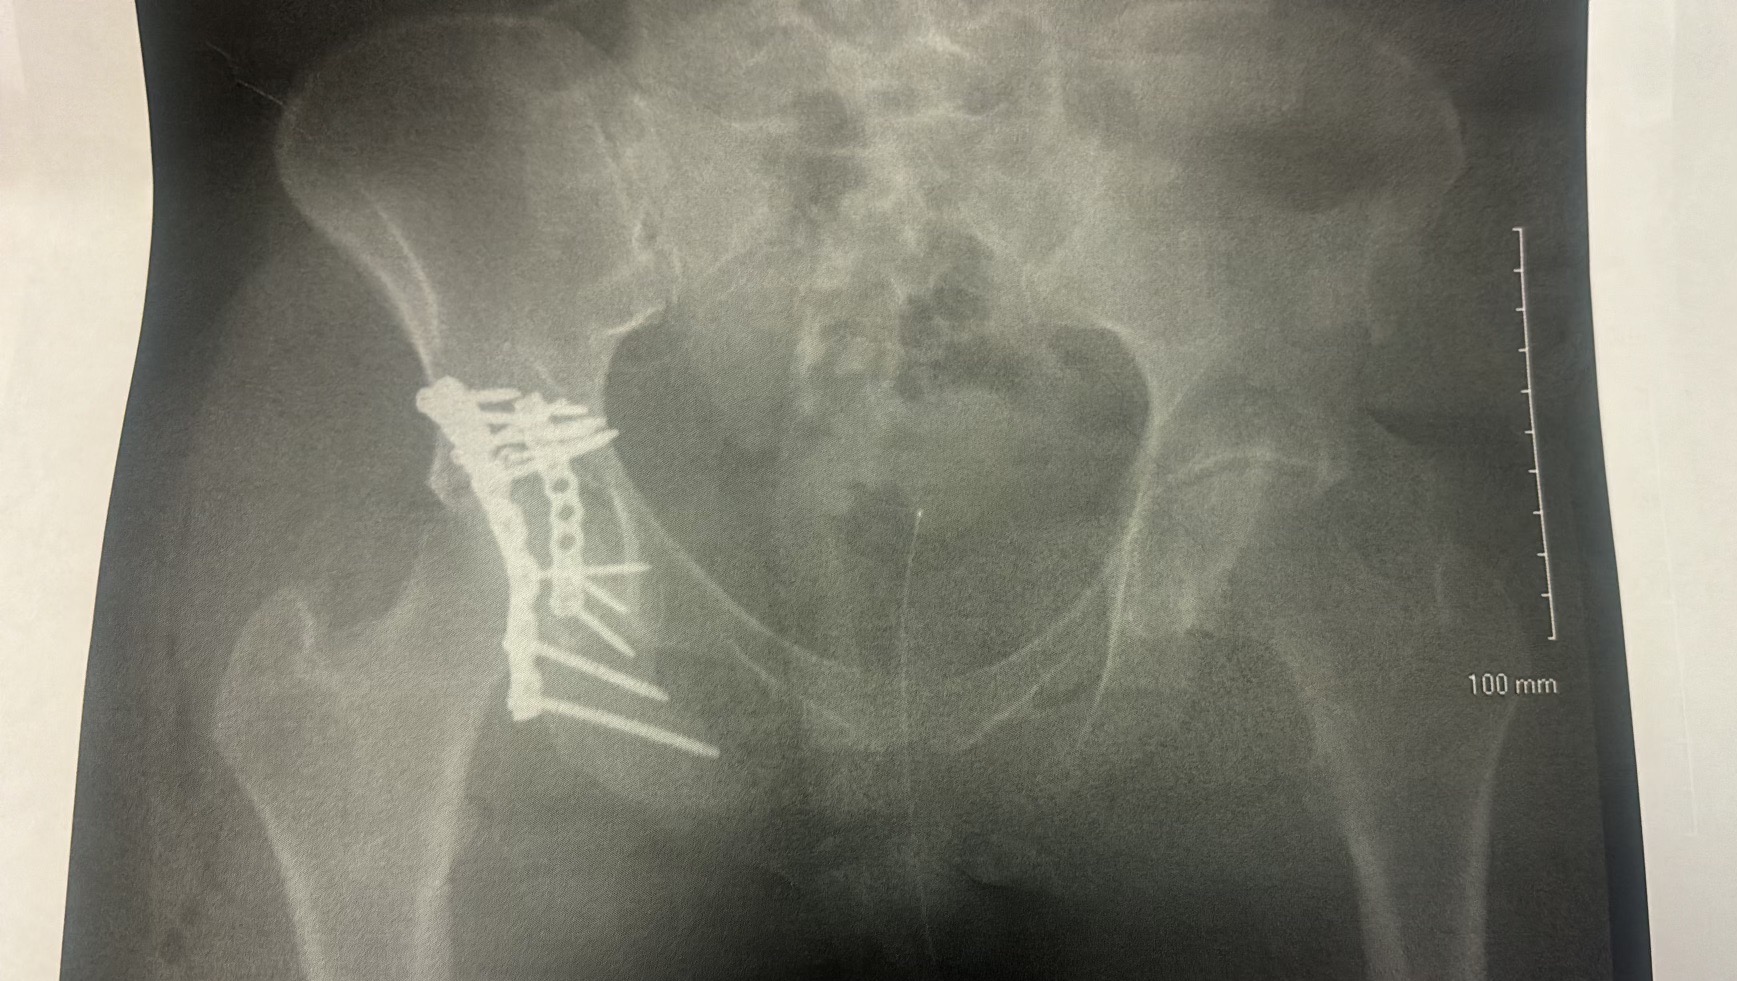

The accident caused a severe pelvic fracture, and she had to undergo a major surgery in which doctors stabilized her pelvis with 12 metal bolts and 2 metal plates. The procedure also required around 50 stitches.

El accidente le causó una fractura severa en la pelvis, por lo que tuvo que someterse a una cirugía mayor en la que los médicos estabilizaron su pelvis con 12 tornillos de metal y 2 placas metálicas. La operación también requirió alrededor de 50 puntos de sutura.